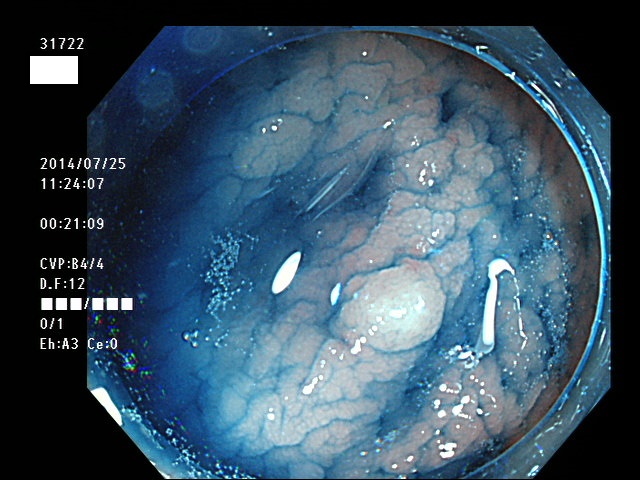

微小カルチノイドの診断

直腸の微小カルチノイドの診断は最も難しい問題です

微小とはいえ、カルチノイドは悪性であり、肛門に近い場所に好発するために、見落とすと数年後には「人工肛門」になる危険があります

進行したカルチノイドの診断は容易なのですが、カルチノイドは「粘膜下腫瘍」と言いまして、は表面が正常粘膜で被われているために微小ですと「単なる過形成結節」「単なる炎症性の隆起」と区別がつかないのです

下記の写真は全て、当院で診断された微小カルチノイド(悪性)ですが、いかに診断が困難かお分かりいただけるでしょう。このような微小病変でさえも見落とせば人工肛門の危険が潜んでいる訳です。